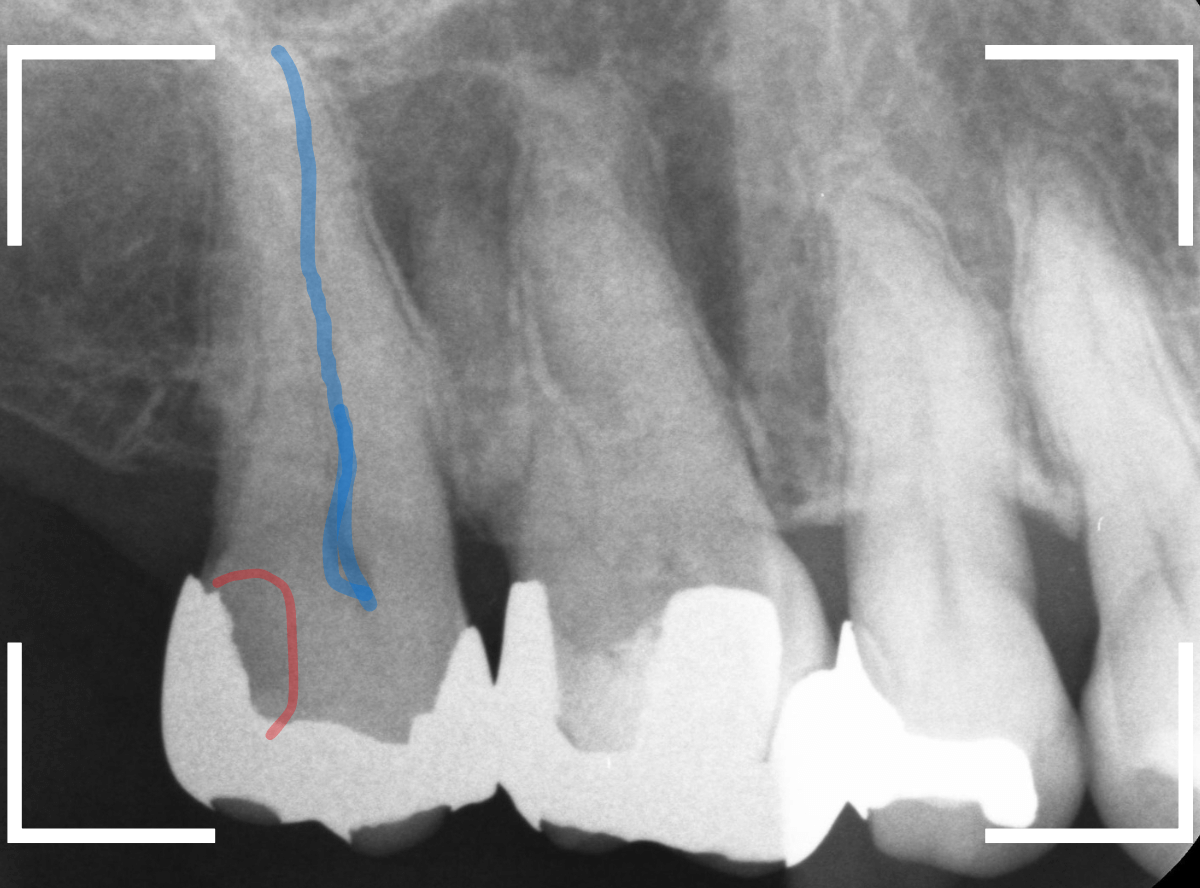

レントゲン写真で確認します。

やはり、奥歯の端が大きな虫歯になっています。

青いラインが歯の神経、赤いラインが虫歯です。

レントゲン写真上では虫歯が神経まで達しているように見えます。

これは、神経を取らないとダメかもしれません。